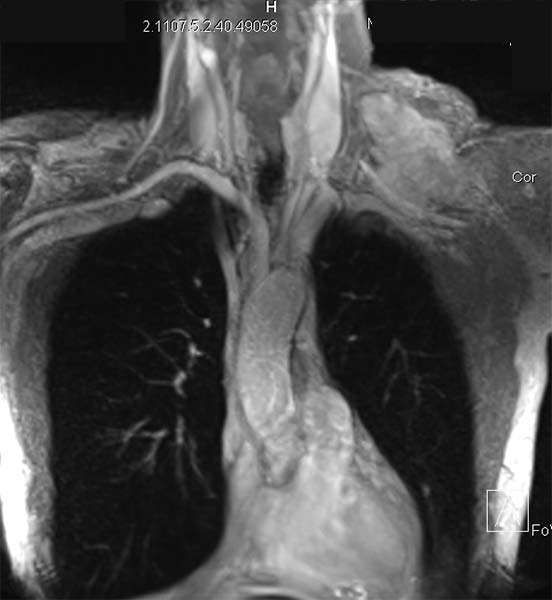

Surgery was performed with curative intent. The patient was positioned supine with the neck fully extended and the head turned away from the tumor. The tumor was approached through the anterior trans-cervical approach described by Dartevelle. This approach allowed us to dissect the subclavian vascular bundle and the nerve roots of the brachial plexus freely, quickly and safely without sacrificing the radical intent of the operation. After assessing the extent of the tumor from inside and outside of the chest, the lateral arches of the first, second and third ribs were cut and removed en-bloc with the surgical specimen (Figure 2). Due to the high risk of de-stabilizing the shoulder girdle after resection of the first three ribs, clavicle division and muscle resection, we reconstructed the chest wall and clavicle using the Stratos™ titanium bars and clips (Strasbourg Thoracic Osteosyntheses System; MedXpert, Heitersheim, Germany) (Figure 3). The chest wall defect and the reconstructed clavicle were covered with polytetrafluoroethylene (PTFE) patches (Figure 4).